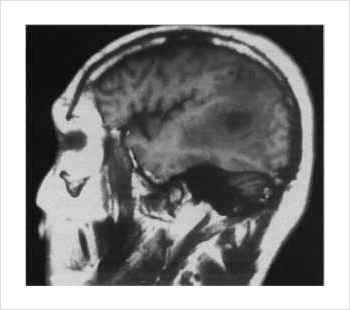

Среди методов, регистрирующих электрическую активность, широко распространена электроэнцефалография, которая позволяет отобразить активность человеческого мозга. «Заглянуть в чужую голову», а, впрочем, не только в голову, позволяют методы томографии. Само слово «томография» означает «изображение среза». Это значит, что задачей томографии является получение послоевого изображения исследуемого объекта, органа.

позволяет получать изображение срезов

разных органов, в том числе и головы

Современная томография для получения информации использует внешнее излучение разной физической природы. Это ультразвук, радио- и оптические сигналы, гамма-лучи, корпускулярное излучение, акустические волны и т.д. Для каждого вида излучения характерны свои особенности, которые и диктуют требования к постановке томографического эксперимента и конструкции прибора.